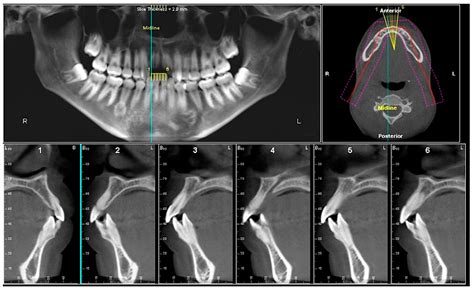

Cone Beam CT is a specialized type of X-ray imaging system used when regular dental or facial X-rays are not sufficient. The technology derives its name from the shape of the X-ray beam, which is emitted in a cone shape. During the scan, the machine rotates around the patient’s head, capturing hundreds of images from various angles in a single rotation. These images are then reconstructed by computer software into a highly detailed 3D model of the patient’s teeth, jawbone, soft tissues, nerve pathways, and nasal cavity.

- Dental Implant Planning: Surgeons can precisely measure bone density and volume, ensuring implants are placed in the ideal position while avoiding vital anatomical structures like the mandibular nerve.

- Orthodontic Treatment: By analyzing the 3D position of teeth and the relationship of the jaws, orthodontists can create more predictable treatment plans for malocclusions and skeletal discrepancies.

- Impacted Tooth Assessment: It is crucial for visualizing the exact position of impacted wisdom teeth and their relationship to the inferior alveolar nerve.

One of the most profound benefits is the diagnostic accuracy. Because the technology is not subject to the magnification or distortion inherent in 2D panoramic X-rays, measurements taken from a Cone Beam CT image are essentially 1:1 scale. This precision is vital for the success of complex surgeries, where millimeters can make the difference between a successful implant integration and nerve damage.